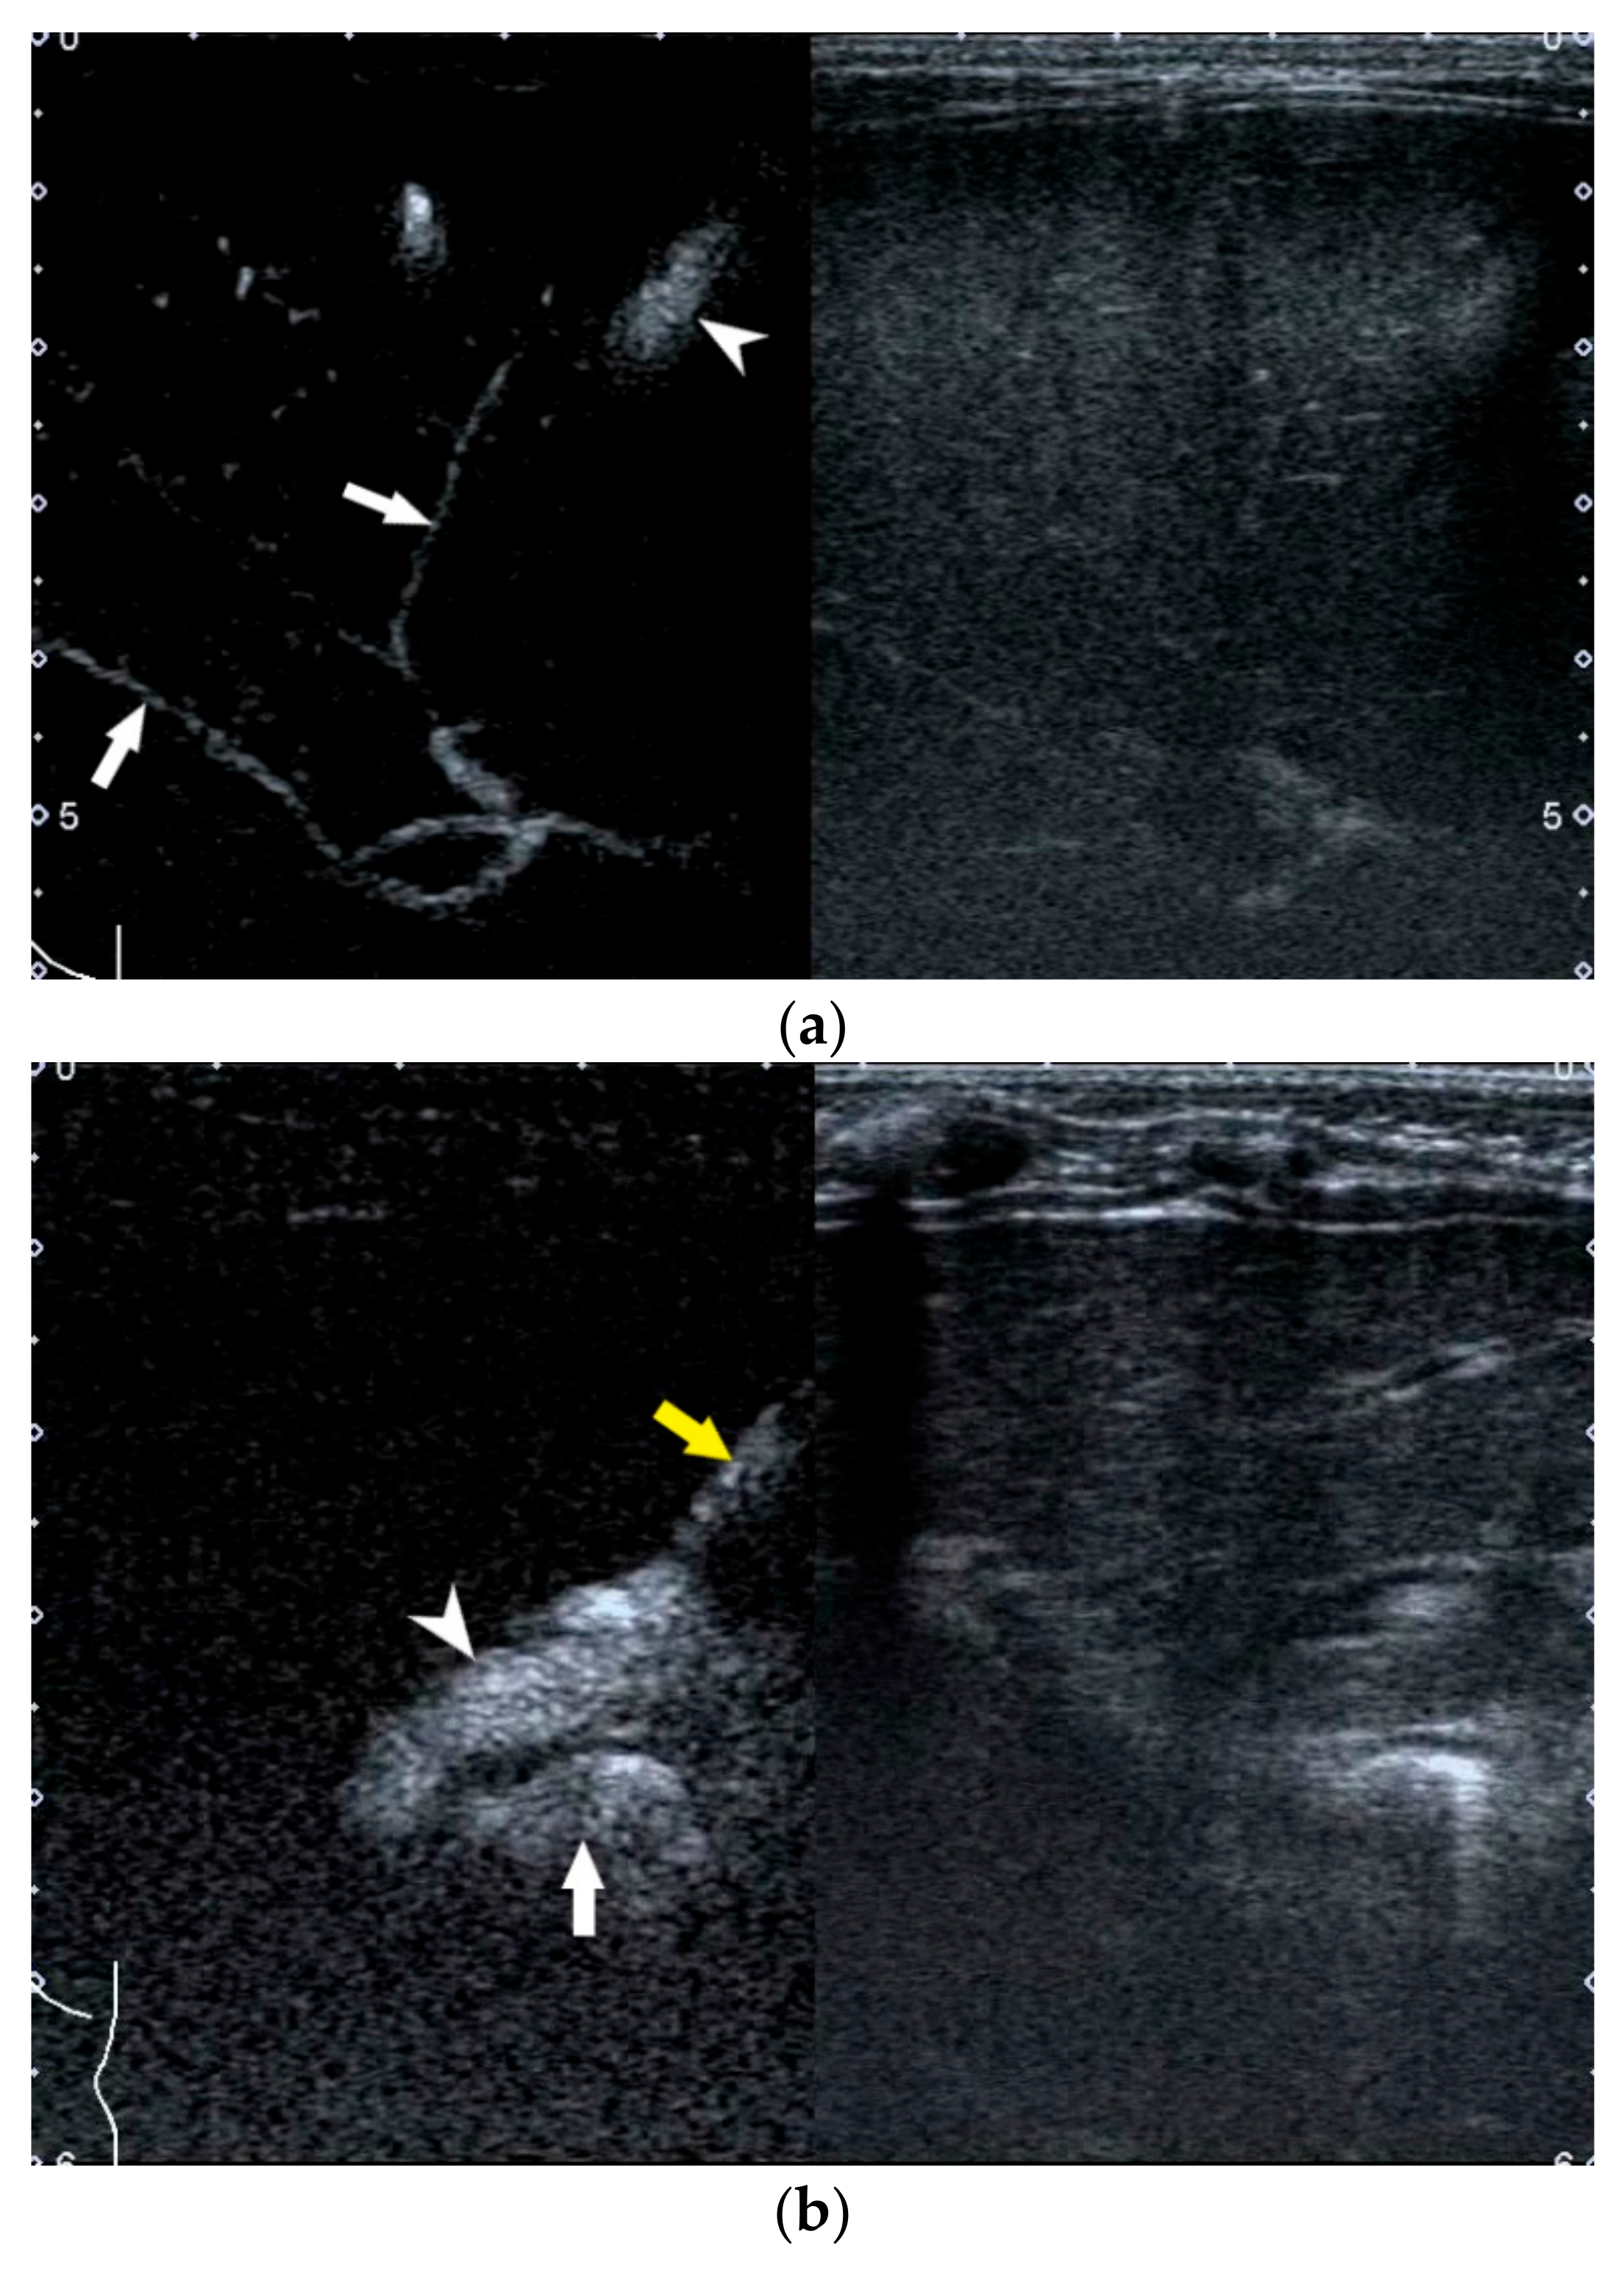

2.3. Porta Hepatis Macro- or Microcyst

- Koob, M.; Pariente, D.; Habes, D.; Ducot, B.; Adamsbaum, C.; Franchi-Abella, S. The porta hepatis microcyst: An additional sonographic sign for the diagnosis of biliary atresia. Eur. Radiol. 2017, 27, 1812–1821. [Google Scholar] [CrossRef]

- Shan, Q.-Y.; Liu, B.-X.; Zhong, Z.-H.; Chen, H.-D.; Guo, Y.; Xie, X.-Y.; Zhou, W.-Y.; Jiang, H.; Zhou, L.-Y. The Prognosis of Type III Biliary Atresia with Hilar Cyst. Indian J. Pediatr. 2021, 88, 650–655. [Google Scholar] [CrossRef]